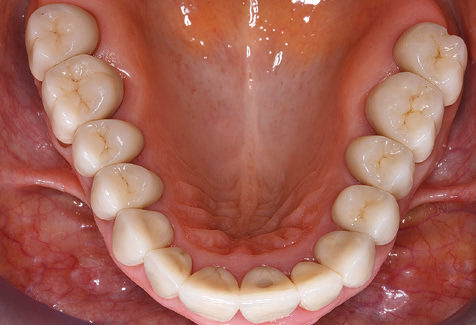

Standardised and regular risk-adapted care in the scope of SPT is the key to treatment success for the clinical long-term success in periodontically compromised patients. This is particularly true for patients fitted with implants following successfully completed periodontal treatment (Fig. 11a and b).

Before initiating the prosthetic treatment, it is advisable to inform the patient of the time and financial costs associated with the SPT (two to four SPT sessions per year for the rest of his/her life). This contributes significantly to ensuring the patient’s compliance. In addition, the practice is required to provide the rooms and staff necessary for the care of the periodontically treated patients.